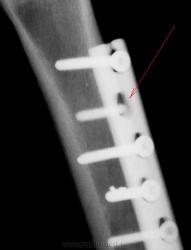

Ирония в том, что в проекции четвёртого и последнего шурупов (счет сверху) отломки свёрел, а у второго шурупа отсутствует "шляпка". А в остальном действительно хороший остеосинтез.)))

Здравствуйте, Валентин Львович, и спасибо за иллюстрации. У меня видимо другой  графический редактор,ну нет там стрелочек((((. А посмотрите нижний шуруп,там их не два , там рядом часть сверла...

Да, часть "обломанного сверла" видна. Потом, видимо, спишут на инопланетян, я имею в виду , и обломанну. шляпку шурупа, и обломанную часть сверла.

Слава усердным травматологам, не жалеющих сил при закручивании шурупов, и в порыве усердия, ломающих сверла, и оставляющих их в кости, по всей видимости, дабы "укрепить".